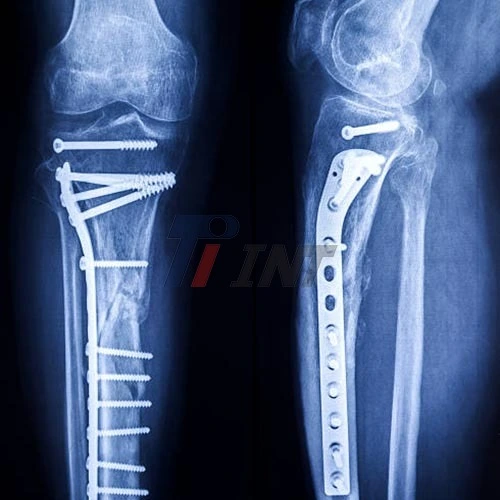

Having a titanium plate in leg can be a life-changing experience. Whether you've suffered a severe fracture or undergone orthopedic surgery, the insertion of a titanium plate is a common medical procedure designed to stabilize and support bone healing. This article will delve into the realities of living with a titanium plate in your leg, exploring the recovery process, potential sensations, and long-term implications.

The prepare of accepting a titanium plate in your leg ordinarily starts with surgery. Orthopedic specialists utilize these plates to hold broken bones in put, permitting them to recuperate legitimately. The method itself is as a rule performed beneath common anesthesia, and patients frequently wake up with their leg immobilized in a cast or brace.

During this time, patients often report a variety of sensations in their leg. Some describe a feeling of tightness or pressure where the titanium plate is located. Others may experience occasional twinges or a dull ache, especially during changes in weather or after prolonged activity. These sensations are generally normal and tend to diminish over time as the body acclimates to the implant.